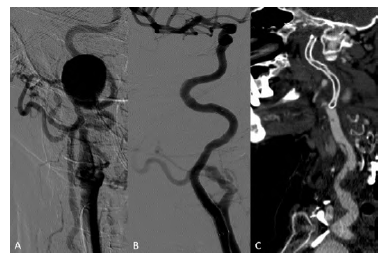

77-year-old female with a history of non-Hodgkin lymphoma treated with chemotherapy presented with facial pain compatible with trigeminal neuralgia. Angio-CT scan showed a 27mm type I aneurysm of the petrous segment of the internal carotid artery (ICA), confirmed by angiography (Figure 4A). No other aneurysms were found, and potential etiologies such as vasculitis were excluded.

Endovascular aneurysm exclusion using a self-expandable covered stent was performed through a cervical carotid surgical approach (Figure 4B) to avoid aortic arch manipulation. ICA catheterization was achieved with a hydrophilic guidewire supported by a Berenstein catheter but with wire coiling within the aneurysm. A 4mm balloon was inflated in the distal ICA to anchor a catheter, allowing the exchange to a Terumo® Stiff guidewire to support the deployment of the stentgraft Viabahn 5x100. Stent occlusion and common carotid artery dissection, presumably related to the puncture site were observed in the postoperative angio-CT (Figure 4C) but without neurological symptoms and with resolution of complaints associated with neurological compression. Dual antiplatelet regimen, initiated in the immediate postoperative period, was suspended after stent occlusion, and the patient was kept under single antiplatelet with acetylsalicylic acid.

Figure 4 Digital subtraction angiography and post-operative computed tomography angiography of a type I aneurysm of the internal carotid artery. A - Pre-operative angiography; B - Completion angiography after aneurysm exclusion with a stentgraft; C - Computed tomography angiography (sagittal view) showing a small dissection of the proximal internal carotid artery and stent occlusion.